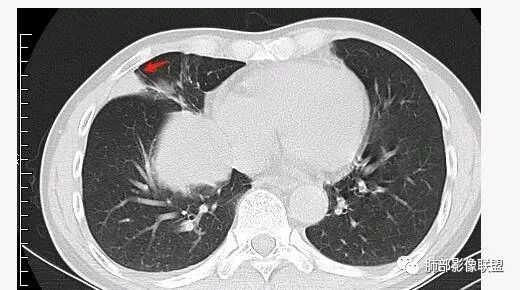

南边:深分叶、大肿块

南边:主体在下叶前基底段

南边:边缘膨隆

南边:中叶、下叶背段支气管推移

南边:中叶支气管腔内似有粘液栓,外侧段有炎性病变

南边:有老师问为啥考虑中叶支气管受压?不是支气管来源的?

1、主体病灶在下叶

2、支气管腔还在,有移位

但是现在的片显示,其主体在下叶,中叶支气管壁由下朝上有推移

南边:病灶边界清,提示侵袭性弱,膨胀生长为主;这时候我们提示病灶不应该是支气管关系密切,提示间叶来源或胸膜来源

深分叶,警惕恶性